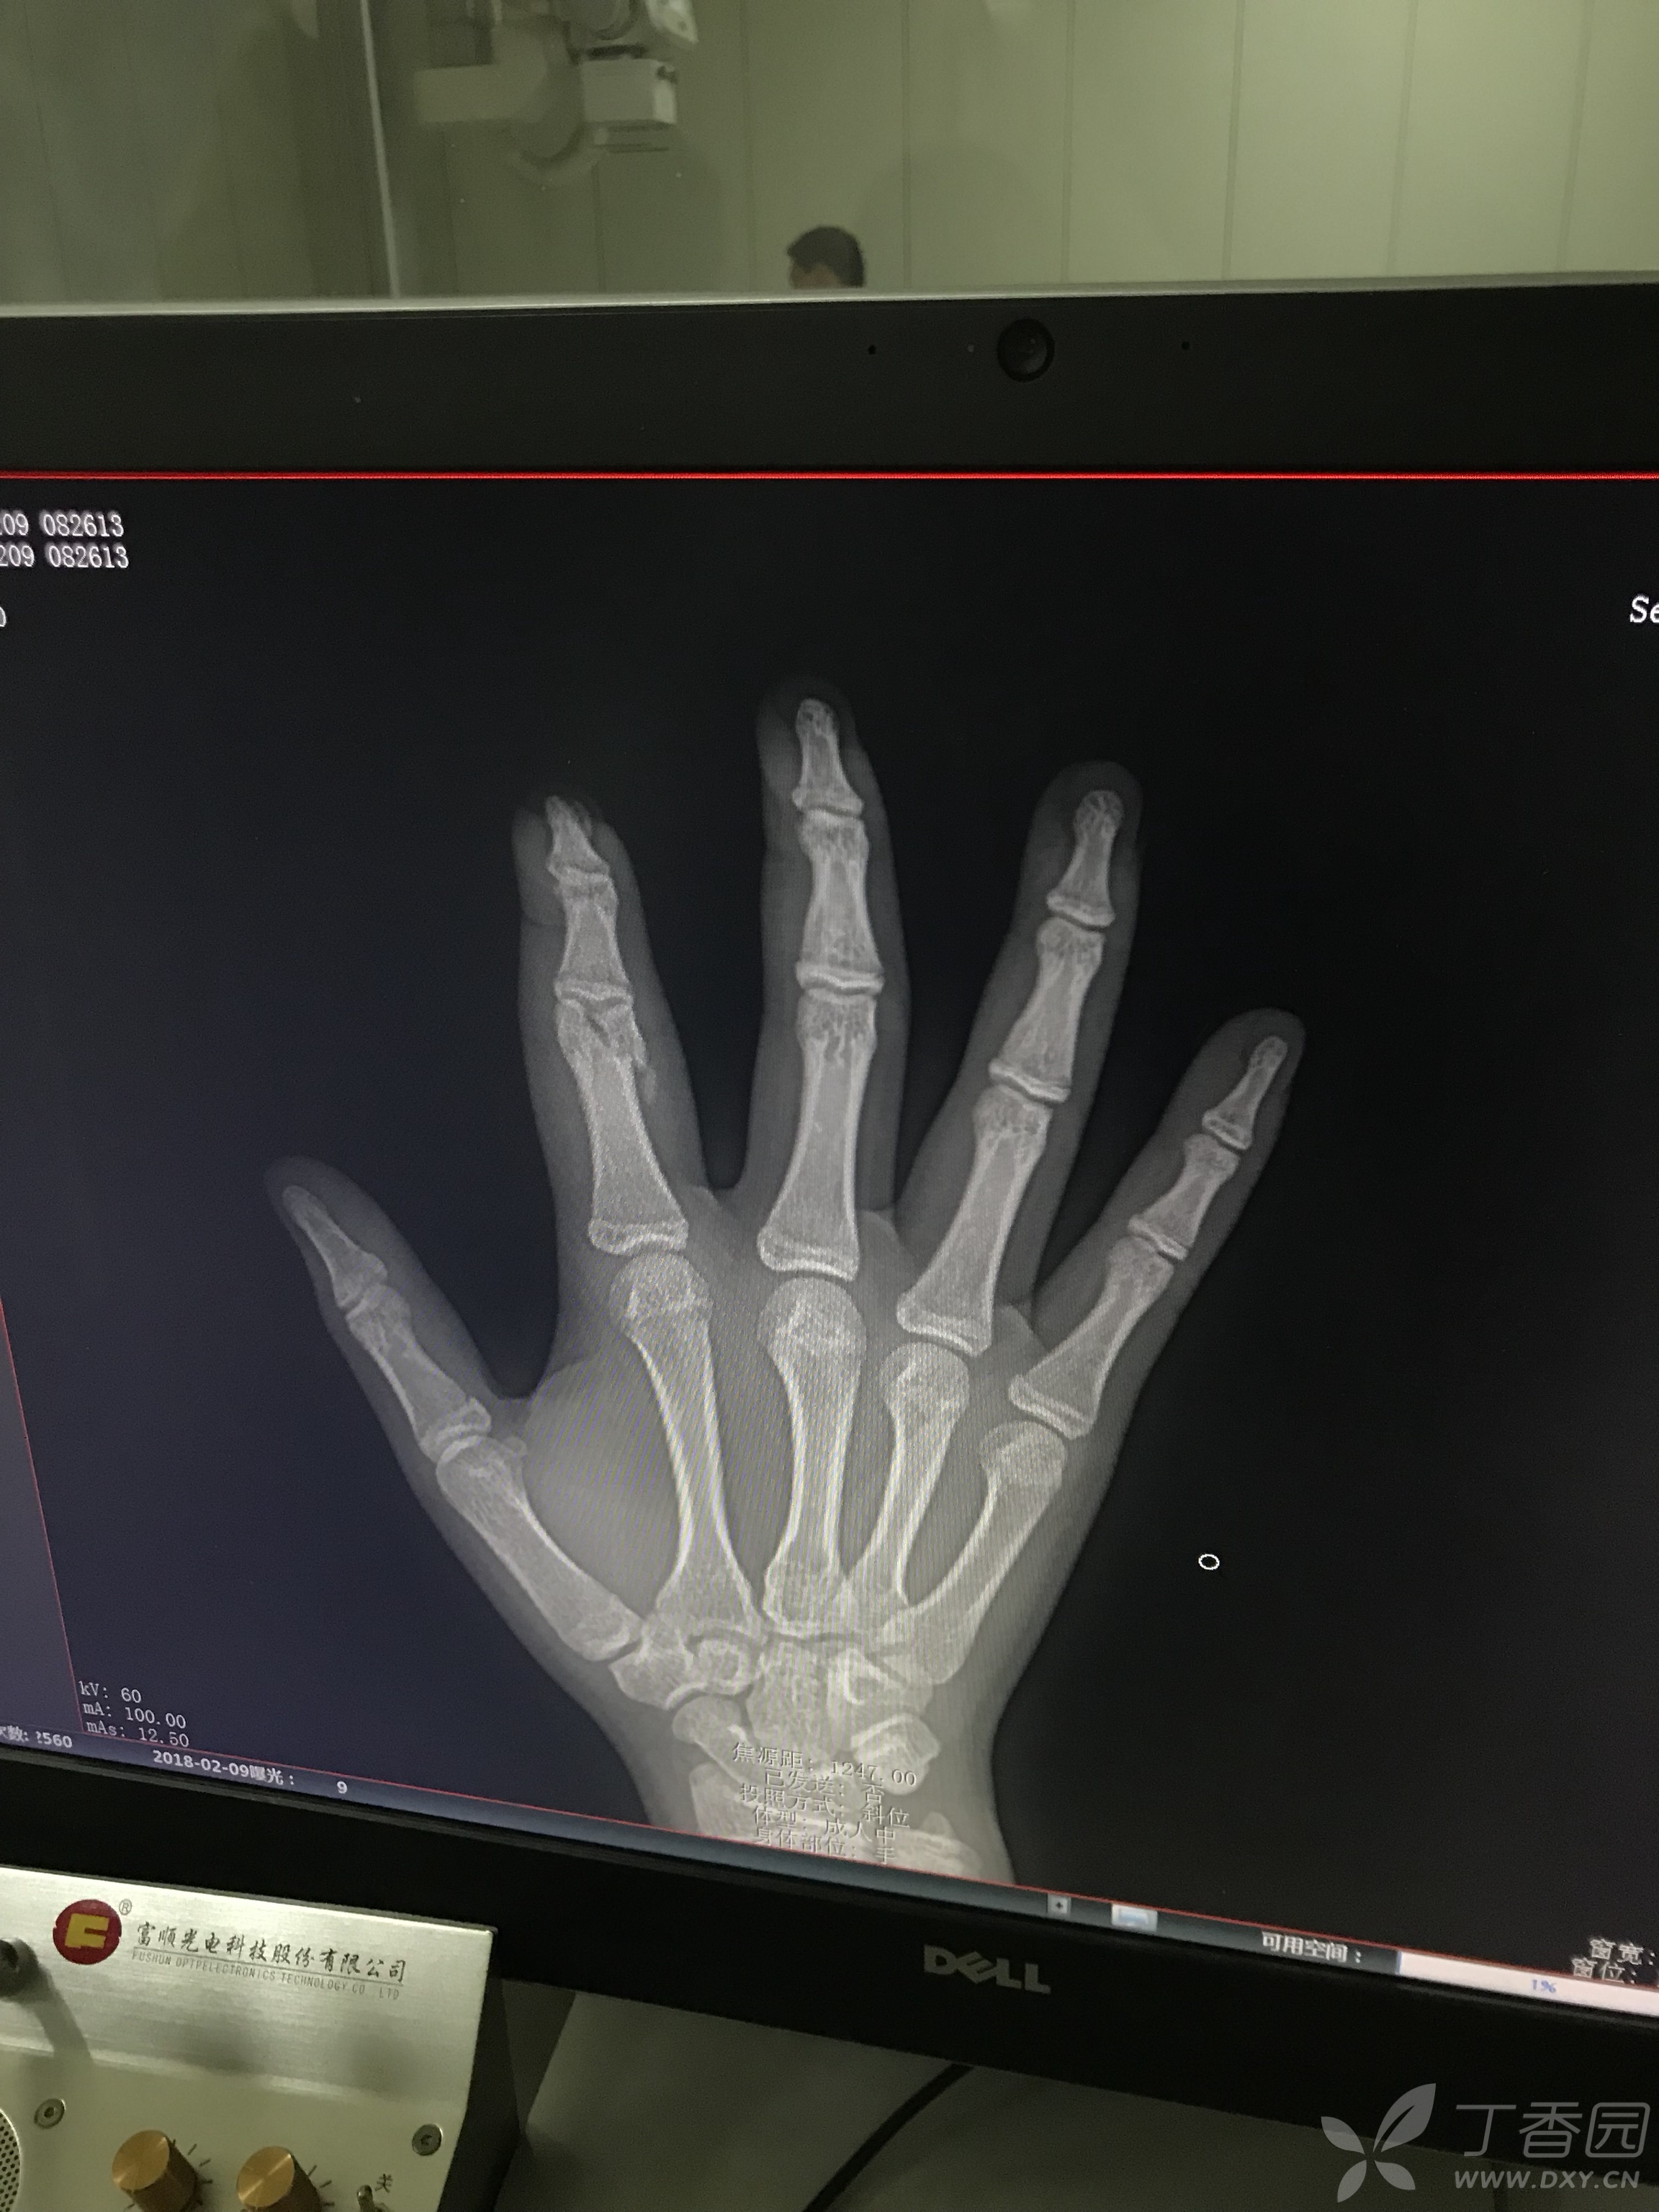

右手骨裂x光图片

右手骨裂x光图片,手骨x光图片

手骨x光图片

手骨裂x光片